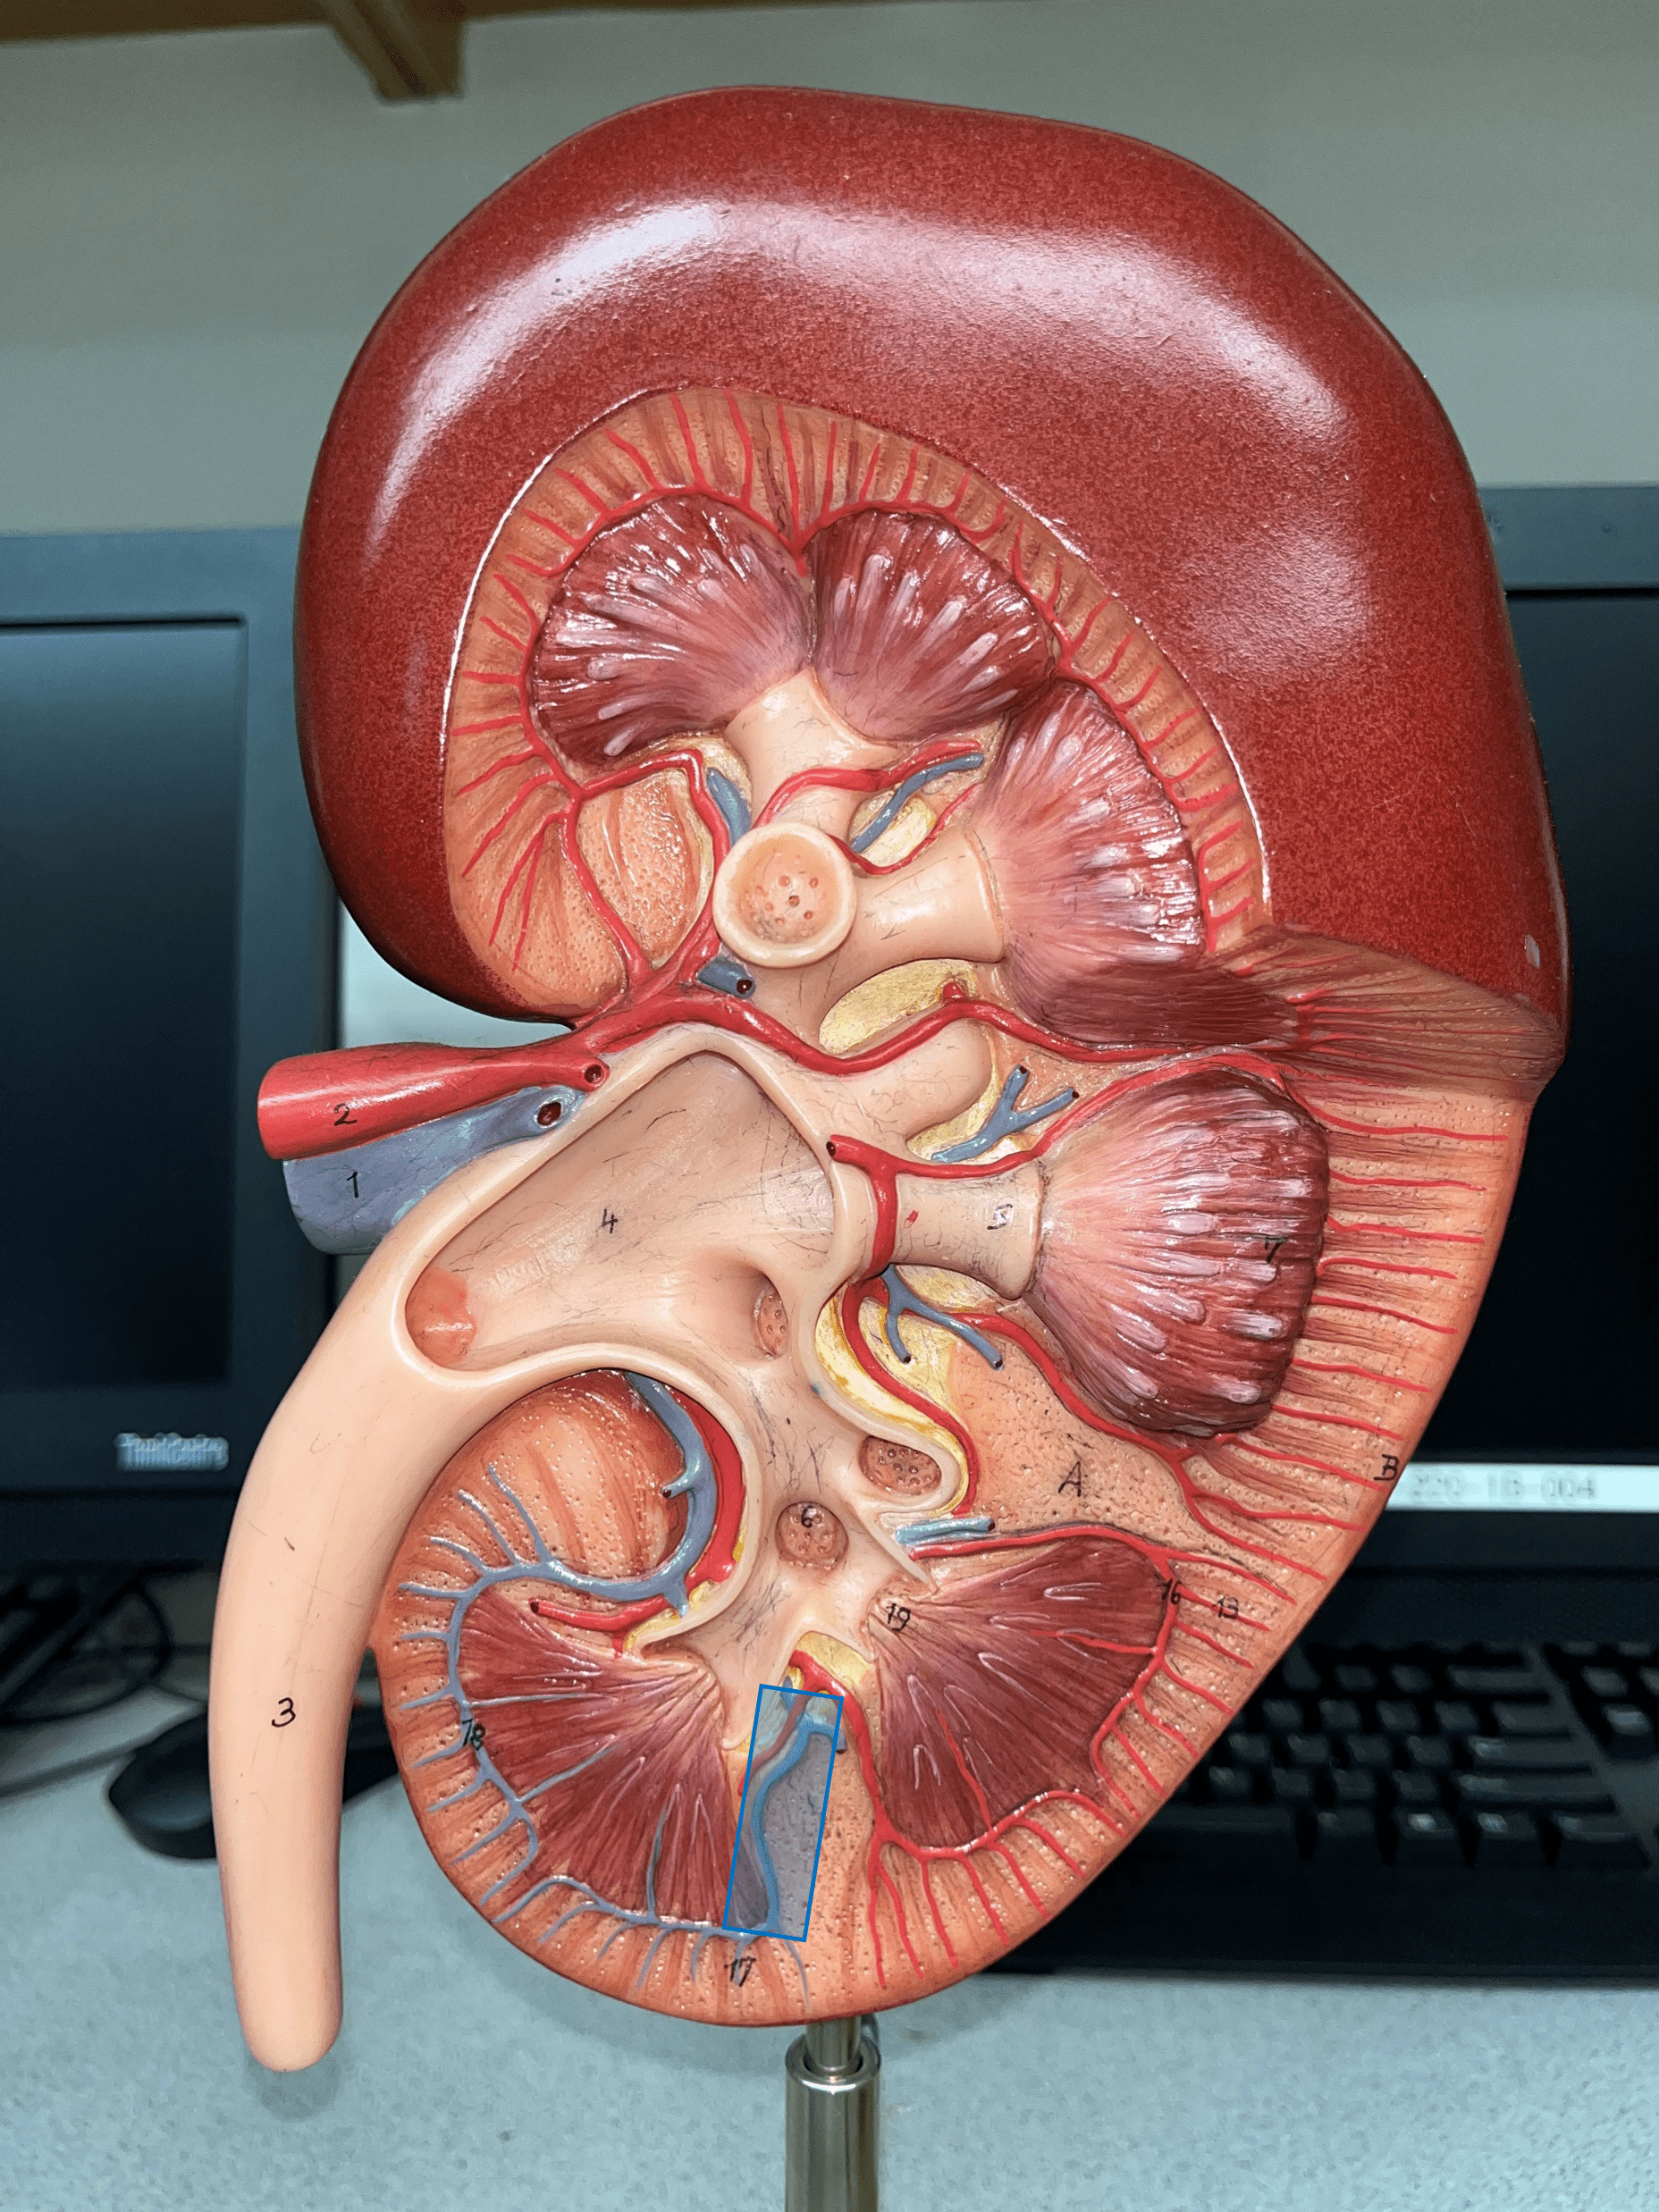

interlobar vein

arcuate vein

interlobular vein

renal pyramid

renal papilla

renal medulla